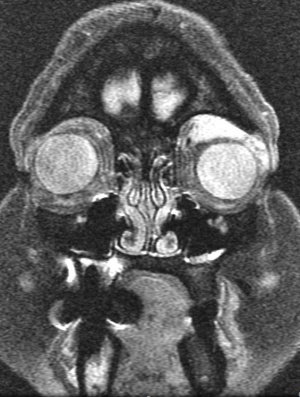

Diagnosis of orbital plasmacytoma can only be made with histopathologic examination of a biopsy of the lesion although classic radiologic features in a patient with or without known multiple myeloma may be suggestive as well. Plasmacytomas are found in the posterior orbit 69% of the time and are extraconal 90% of the time.[6] Most commonly, patients have a superotemporal bony lesion involving the sphenoid or frontal bone with orbital extension causing a mass effect.[6][8] Other radiographic appearances include a lesion infiltrating across anatomical planes including those originating from the sinuses and those emanating from the orbital floor. Bony destruction can be found with these lesions. Additional laboratory tests should be considered in all patients once a diagnosis of plasmacytoma has been established, especially patients without a known history of Multiple Myeloma as a plasmacytoma can be an initial presenting sign.[8] These include tests for anemia, hypoproteinemia, Bence Jones proteinuria, and abnormal proteinemia. Further testing may find hypercalcemia (due to bone destruction), hyperuricemia (resulting from high cell turn over), and elevated ESR. Hypergammaglobulinemia is present in 85% of cases of multiple myeloma.